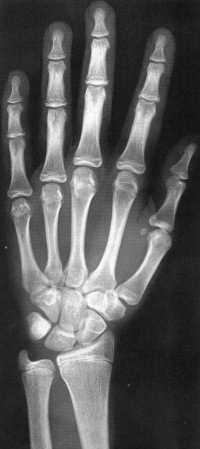

Sexo Masculino

10 anos

11 anos